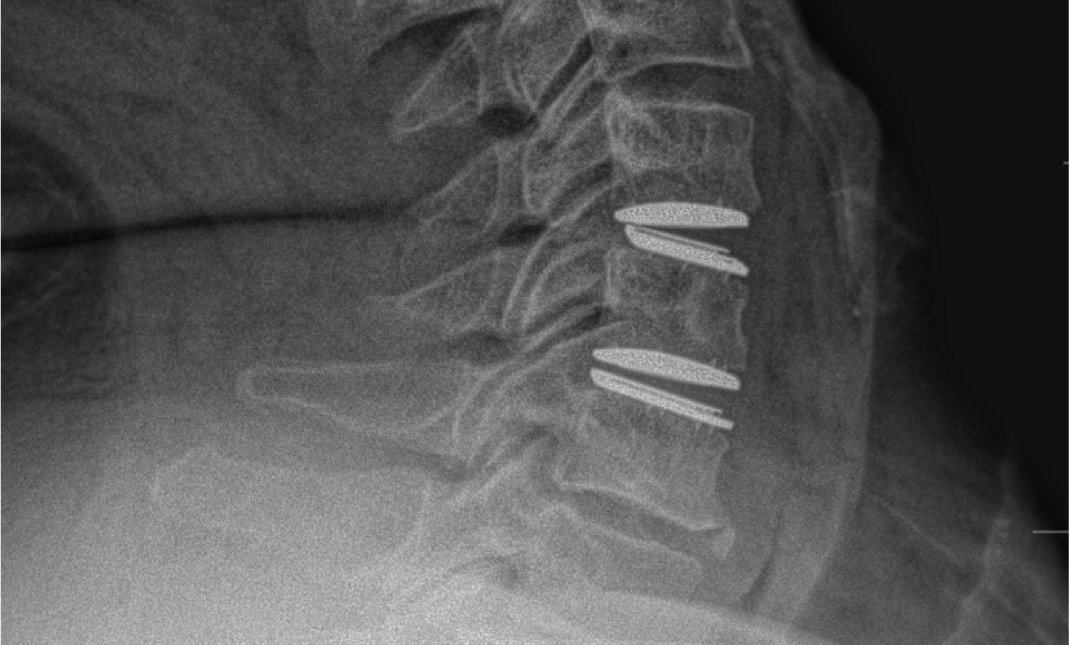

During the procedure, prodisc C Vivo fit well within the C4-5 concave endplate. I expected to use a flat endplate prodisc C SK at C5-6, however I trialed the domed prodisc C Vivo and it actually looked good, so I unexpectedly used matching implants.

It was very helpful to have the flexibility to use either a flat or a domed implant at either level. Having the different size options available to truly match patient anatomy that the Match-the-Disc™ System provides enabled me to avoid having to alter the patient’s anatomy to fit the device.